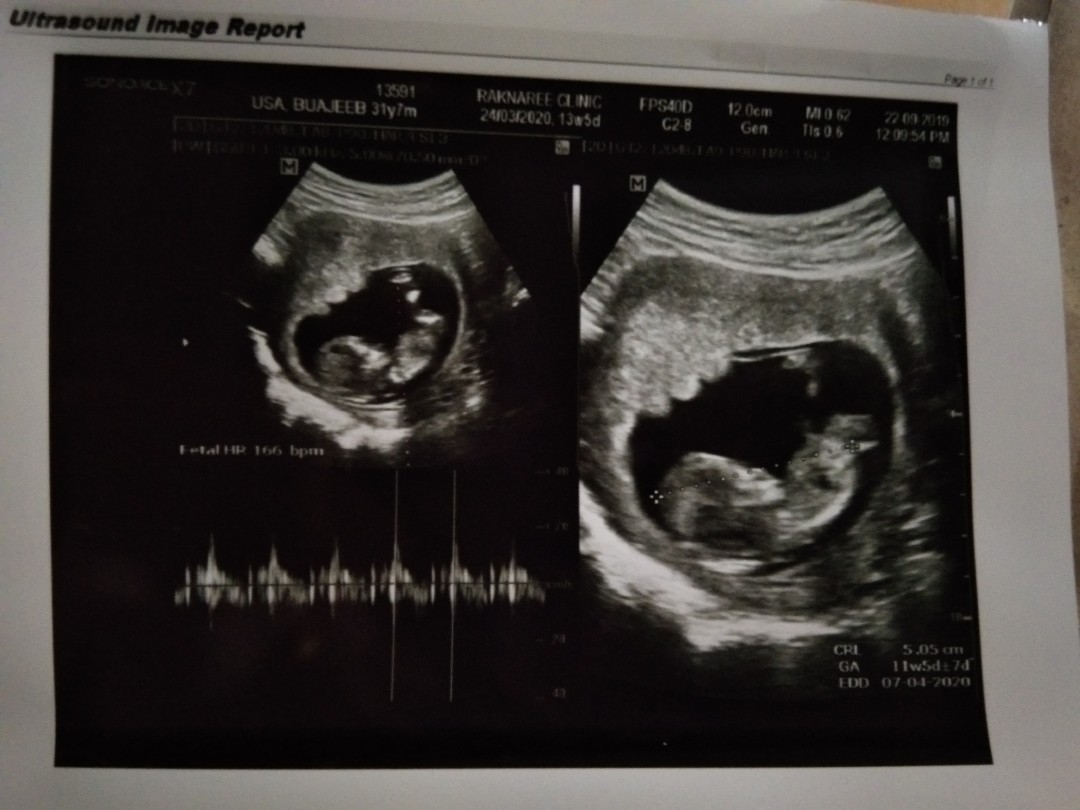

ตอน11wค่ะ